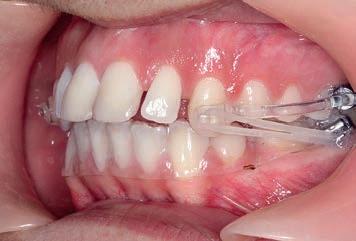

Motion Clear Class II appliance bonded

Treatment commenced with the Motion Clear Class II appliance bonded directly to the upper canines and first molars with 6 oz, ¼ intraoral elastics for the first month and 8 oz, 3/16 elastics for the second and third months, engaged for Class II traction to molar tubes bonded to the lower second molars. An Essix .04 vacuum-formed retainer was employed in the lower arch for maximum anchorage.

3 months: Class I platform achieved

By the end of the first month of sagittal correction, there was already evidence of some derotation of the upper first molar and movement of the buccal segment (molars, premolars and canines) toward a Class I occlusion. Space was also beginning to open between the upper incisors. After

Figs. 9a–c: Situation after 1 month of correction with Sagittal First approach. – Figs. 10a–c: Situation after 2 months of correction. – Figs. 11a–c: Situation after 3 months of correction: Class I achieved. – Figs. 12a–c: Situation after 4 months of treatment (3 months of Motion sagittal treatment and 1 month in fixed appliances). .014 x .025 wire with power chain to close the spaces between the incisors. – Figs 13a–c: Situation after 7 months of treatment (3 months of Motion sagittal treatment and 4 month in fixed appliances). .019 x .025 archwire was engaged with power chain to retract the anterior segment and bring it into the final desired position. – Figs 14a–c: Final situation achieved after 11 months of treatment (3 months of Motion sagittal treatment and 8 months of Carriere SLX fixed appliance therapy).